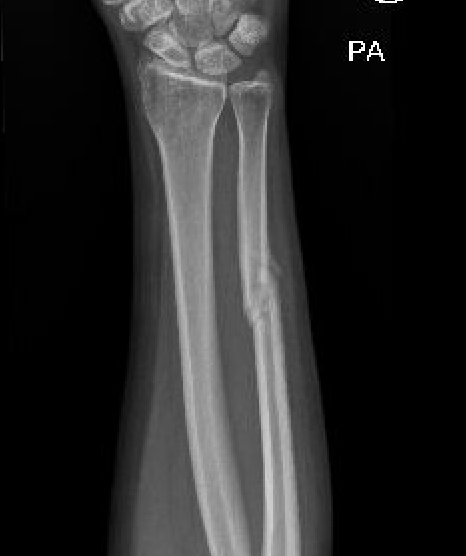

Increased nonunion rates with midshaft versus distal fractures

Henry et al J Hand Surg Am 2023

- 95 isolated ulna fractures

- union rate nonoperative: 91%

- union rate operative: 97%

- increased nonunion with midshaft (30%) versus distal 1/3 fractures (2%)